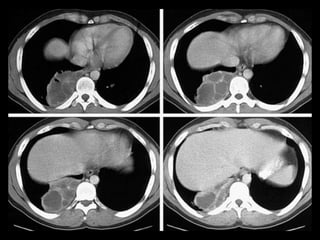

Cisto Broncogênico(CB)

É de longe a forma mais comum de cisto de

duplicação do intestino anterior resultante de uma

má separação ventral com a árvore

traqueobrônquica;

Cerca de 80% dos casos ocorrem nas regiões

paratraqueal ou subcarinal;

Os CB são malformações císticas congênitas dos

pulmões raras e apenas de 10-30% apresentam

localização intrapulmonar;

Todos os CB apresentam uma camada de epitélio

respiratório e podem conter cartilagem;

Caracteristicamente, os CB não se comunicam com a

árvore traqueobrônquica até que se tornem

infectados;

Os CB n parênquima pulmonar podem estar

associados à hiperinsuflação e ao aprisionamento

aéreo, como resultado de um mecanismo de válvula

ou atelectasia pós-obstrutiva.

Nível hidroaéreo: leite de cálcio